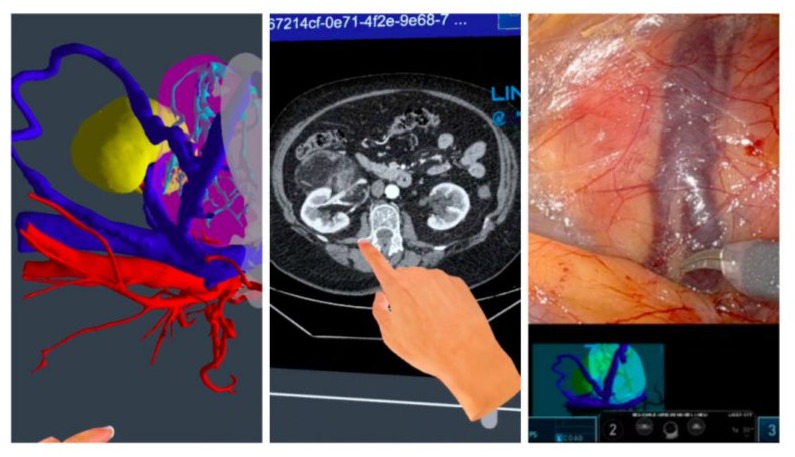

The lesion on patient C patient was of a slightly smaller size, so we decided to underwent a robotic partial nephrectomy. The procedure was facilitated by a three-dimensional model, which was developed

beforehand using imaging tests. This model allowed optimal identification and control of the lesion’s neovascularization (figure 6). The surgery was completed without complications and the patient was discharged on the third postoperative day.

Figure 6: Correlation between preoperative 3D reconstruction and CT scan with intraoperative findings.